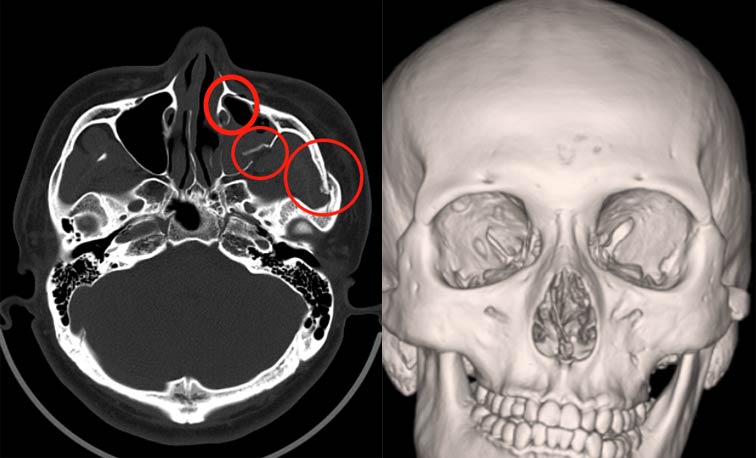

“车门杀”致面部多处骨折,耳鼻咽喉科完成颌面创伤修复

近日,张先生(化名)在骑电瓶车途中遭遇意外。张先生被突然打开的汽车车门撞倒,左侧头面部及右髋部重重着地,左侧头面部剧痛并伴头部出血,下颌活动严重受限、明显偏斜,颌面部外观畸形,同时出现头晕与右侧髋部疼痛等症状。伤情严重,由120紧急送至我院急诊就诊。